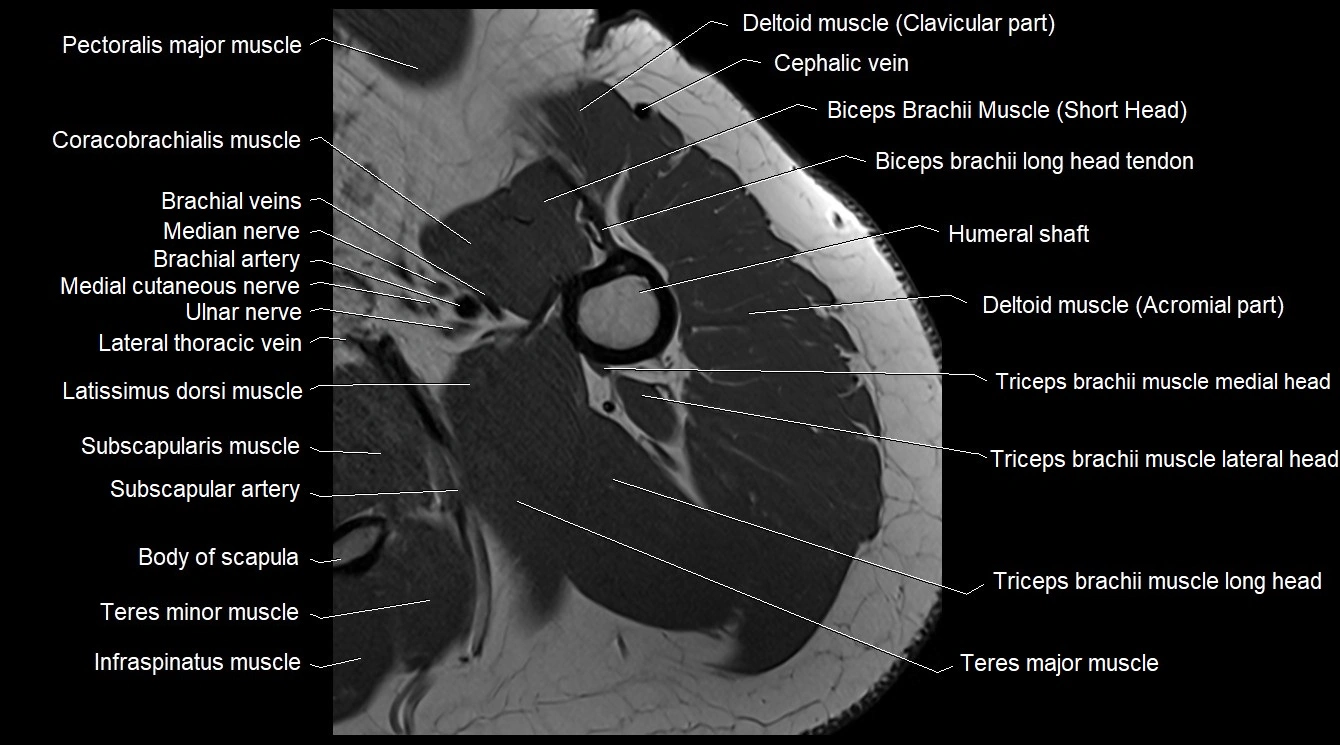

MRI image